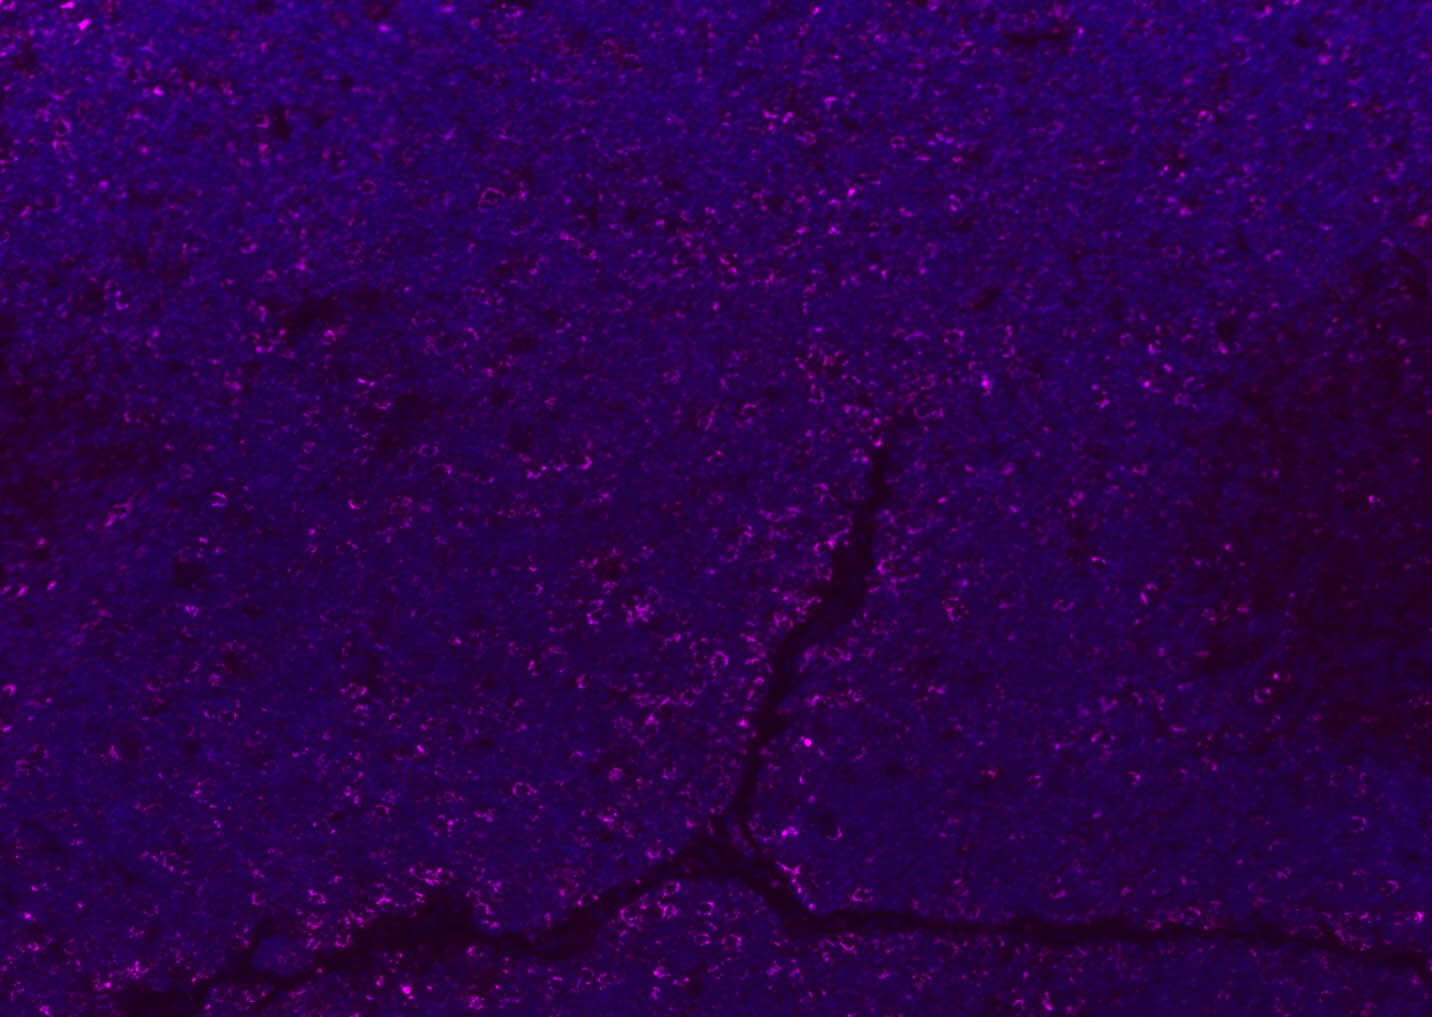

Paraformaldehyde-fixed, paraffin embedded (mouse lymphoid); Antigen retrieval by boiling in sodium citrate buffer (pH6.0) for 15min; Blocking buffer (normal goat serum) at 37°C for 30min; Antibody incubation with (CD8B) Polyclonal Antibody, Unconjugated (bs-4914R) at 1:100 overnight at 4°C, followed by a conjugated Goat Anti-Rabbit IgG antibody (bs-0295G-AF647) for 90 minutes, and DAPI for nuclei staining.